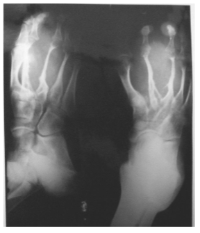

Dermatofibroma Of The Foot Mimicking Neurofibroma Radiologically

Dr. Agunloye A. M., O. M. Atalabi, A. O. Ogunseyinde, M. O. Obajimi, A. O. Adeyinka (Author)

14-15